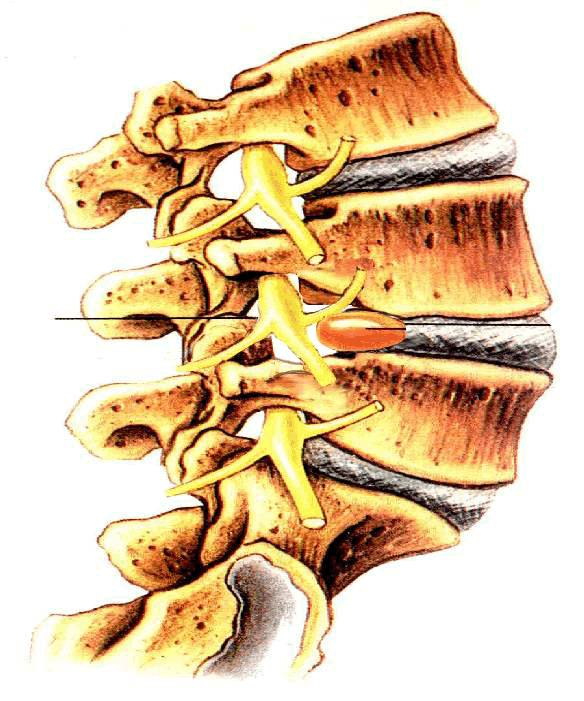

神经根被嵌压于膨出椎间盘和椎弓根之间

A处椎弓根压迫神经根;B处小关节压迫神经根

半脱位的上关节尖端压迫神经根

肥大增生的上关节突压迫神经根